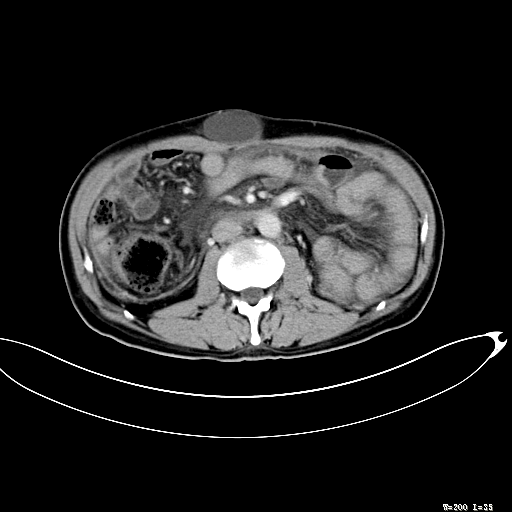

标题: CT27080:腹壁肿物?

男,52岁,门脉高压断流术后1年,发现腹部肿物2月。

1)前腹壁中线区(脐上方)囊性占位性病变,考虑淋巴囊肿。2)腹水。